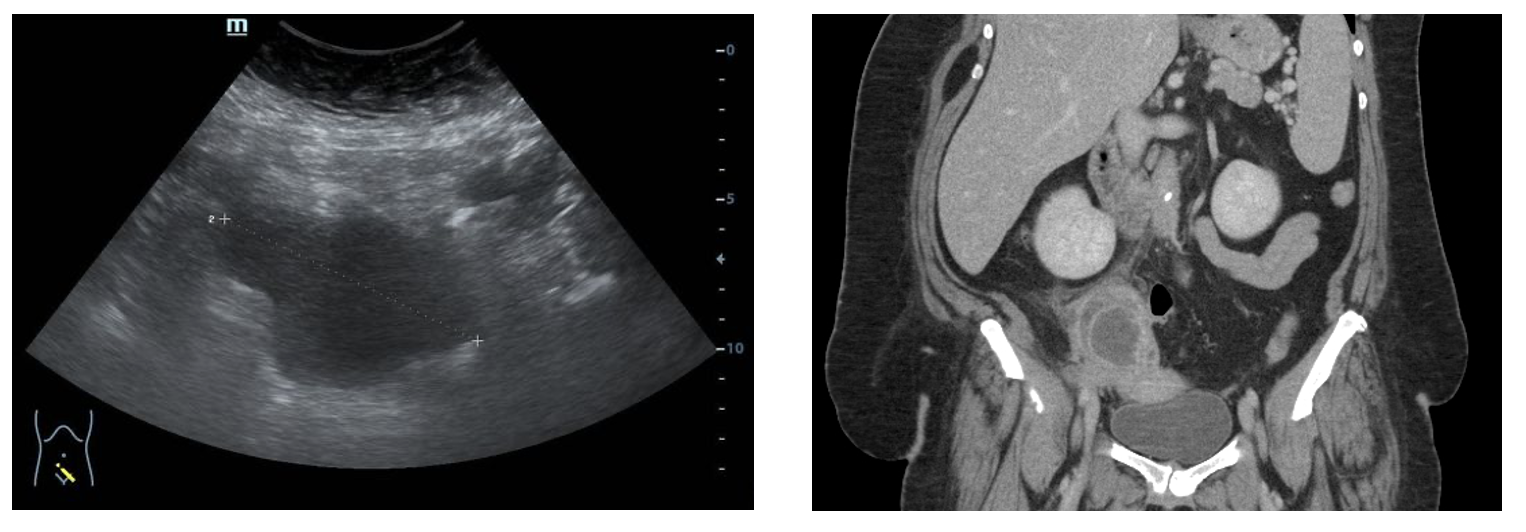

Imaging:

Pelvic ultrasound → first line.

TOA: complex, multilocular, heterogeneous mass distorting adnexal anatomy.

Dilated, thickened, fluid‑filled tubes → pyosalpinx.

Echogenic free fluid in rectouterine pouch → concern for rupture.

CT scan:

Slightly higher sensitivity than US.

Useful for ruling out alternative abdominopelvic diagnoses.

Findings: heterogeneous loculated adnexal mass, thickened rim‑enhancing walls, fat stranding, dilated tubes, pelvic free fluid.